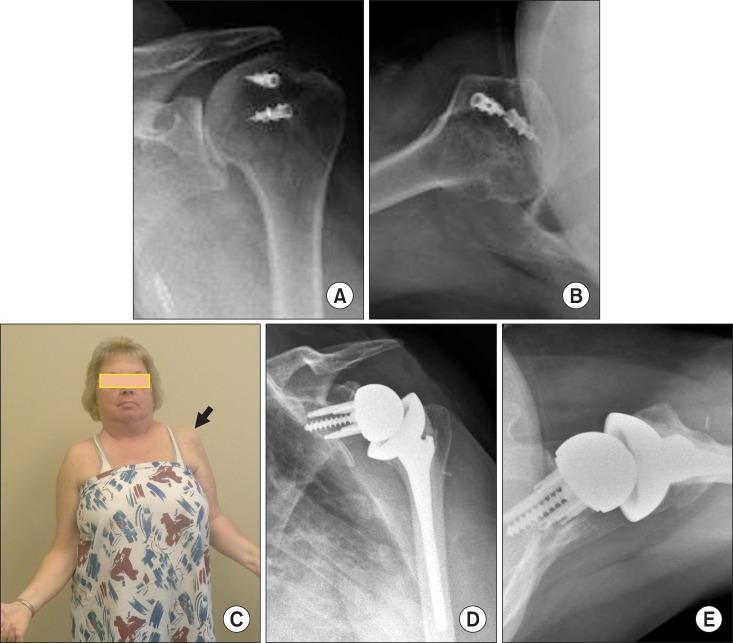

Uncommon indications for reverse total shoulder arthroplasty.

Total shoulder arthroplasty and shoulder hemiarthroplasty have been the traditional method for treating a variety of shoulder conditions, including arthritis, cuff tear arthropathy, and some fracture types. However, these procedures did not provide consistently good results for patients with torn rotator cuffs. The development of the reverse prosthesis by Grammont in the late 20th century revolutionized the treatment of the rotator-cuff-deficient shoulder with arthritis. The main indication for the reverse prosthesis remains the patient with cuff tear arthropathy who has pain and loss of motion. Because the reverse total shoulder arthroplasty produced such good results in these patients, the indications for the reverse prosthesis have expanded to include other shoulder conditions that have previously been difficult to treat successfully and predictably. This review discusses and critically reviews these newer indications for the reverse total shoulder arthroplasty.